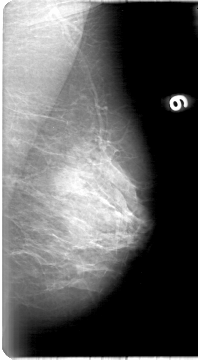

D_4018_1.LEFT_MLO

LEFT_MLO LINES 5386 PIXELS_PER_LINE 2956 BITS_PER_PIXEL 12 RESOLUTION 43.5 NON_OVERLAY